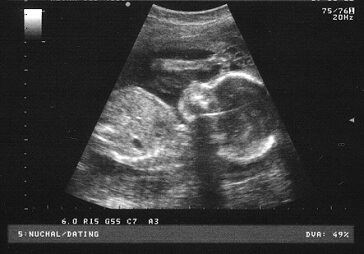

Oligohydramnios is usually detected by ultrasound. The amniotic fluid is measured using an amniotic fluid index (AFI). According to most measurements, less than 6 centimeters is evidence of oligohydramnios.